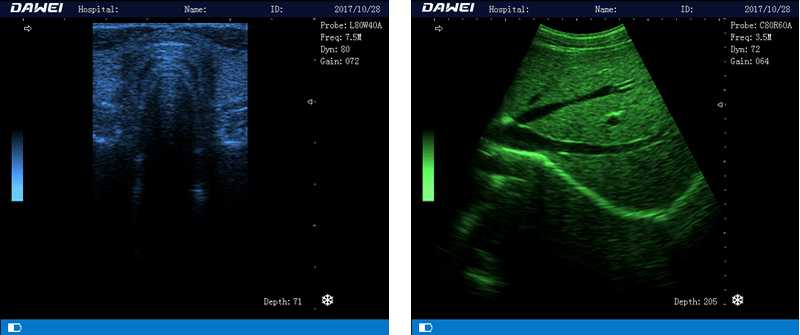

DW-580

筆記本全數字超聲診斷儀

1.優質的數字成像技術,圖像更清晰

2.智能化TGC全程8段增益控制